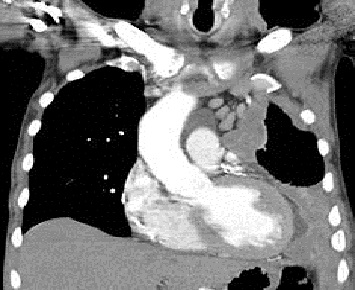

Signs and symptoms of mesothelioma

include shortness of breath due to pleural effusion (fluid between the lung and

the chest wall), chest wall pain and constitutional signs such as unexplained

weight loss. The diagnosis may be suspected based on chest X-ray and CT scan

findings, but must be confirmed either by examining serous effusion cytology or